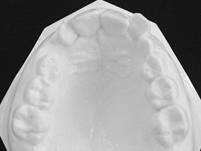

สภาพฟันก่อนรักษา

สภาพฟันหลังรักษา